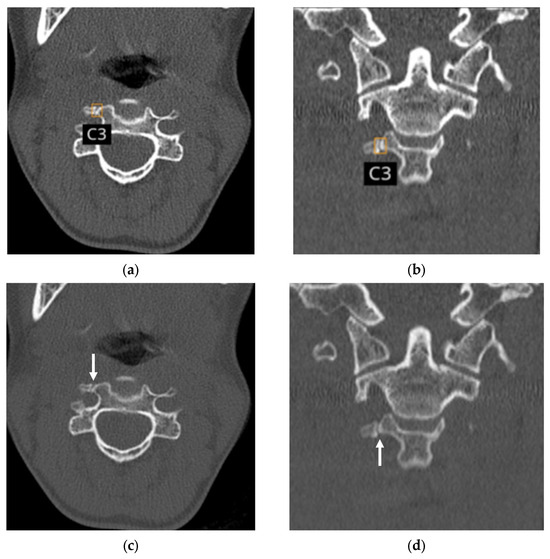

Multicenter, Multinational, and Multivendor Validation of an Artificial Intelligence Application for Acute Cervical Spine Fracture Detection on CT

by Jinkyeong Sung, Peter D. Chang, Angela Ayobi, Martina Cotena, Mar Roca-Sogorb, Jinhee Jang, Daniel S. Chow and Yasmina Chaibi

Diagnostics 2026, 16(2), 194; https://doi.org/10.3390/diagnostics16020194 - 7 Jan 2026

Background/Objectives: While previous studies have evaluated AI algorithms for cervical spine fracture (CSFx) detection on CT, many have lacked validation on diverse, multinational datasets or have focused primarily on overall case-level classification This study aimed to evaluate the performance of an AI application [...] Read more.

Background/Objectives: While previous studies have evaluated AI algorithms for cervical spine fracture (CSFx) detection on CT, many have lacked validation on diverse, multinational datasets or have focused primarily on overall case-level classification This study aimed to evaluate the performance of an AI application for acute CSFx detection in case-level classification, fracture localization, and spinal level labeling on multicenter, multinational, and multivendor CT data. Methods: Non-enhanced CTs were retrospectively collected from a U.S. teleradiology company, a French teleradiology company, and a U.S. university hospital. Four radiologists independently labeled the presence and location (including the spinal level) of acute CSFx to establish the reference standard. Per-case diagnostic performance, per-bounding box positive predictive value (PPV) for localization, and overall agreement of cervical vertebral level labeling of the AI were assessed. Results: A total of 155 patients (60.6 years ± 21.2 years, 104 men) with acute CSFx and 173 patients (51.9 years ± 22.7 years, 91 men) without acute CSFx were evaluated. Data were acquired using scanners from five manufacturers. For acute CSFx diagnosis, the AI achieved a per-case sensitivity of 90.3%, a specificity of 91.9%, an accuracy of 91.2%, an area under the receiver operating characteristic curve (AUC) of 0.91, and Matthews correlation coefficient of 0.82. Among 192 bounding boxes representing acute CSFx generated for 154 positive cases by the AI, 162 were true positives (per-bounding box PPV, 84.4%). Of the 186 bounding boxes for which the AI displayed cervical spinal level, 181 were labeled correctly (overall agreement, 97.3%). Conclusions: The AI application for detecting acute CSFx demonstrated high diagnostic performance on multicenter, multinational, and multivendor data, with high performance in fracture localization and spinal level labeling. Full article

(This article belongs to the Special Issue Contemporary Spine Diagnostics and Management)

Show Figures

Figure 1